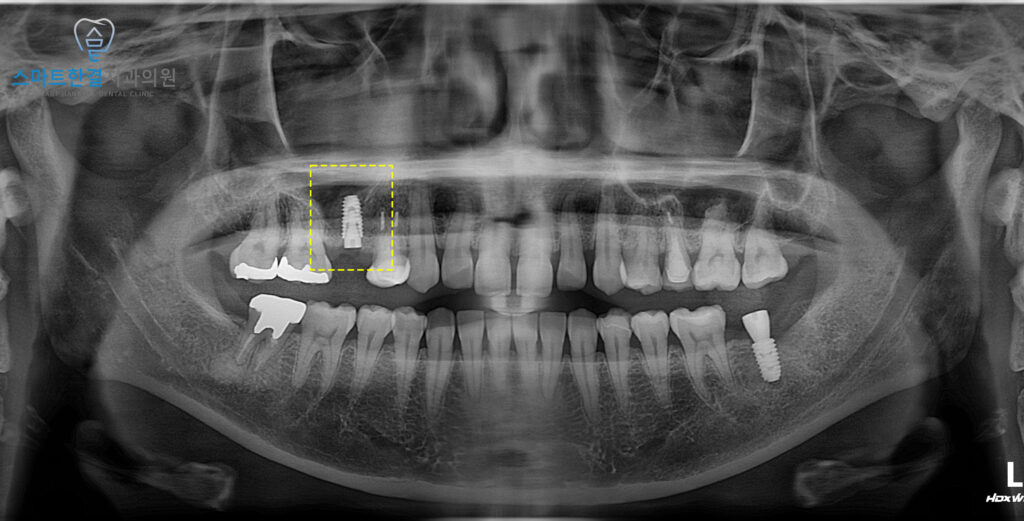

화서동치과 스마트한결치과의

임플란트 수술 전후 사진이에요.

환자분께서는 임플란트 식립뿐만 아니라

상악동거상술까지 진행해야 돼서

무섭고 불안해하셨으나,

수술하면서도 불편함 없으시고

이후에도 괜찮으셔서 다행이라며

만족해 주셨어요.

현재까지 임플란트와 상악동 부위 모두

안정적인 상태를 유지할 수 있었답니다.